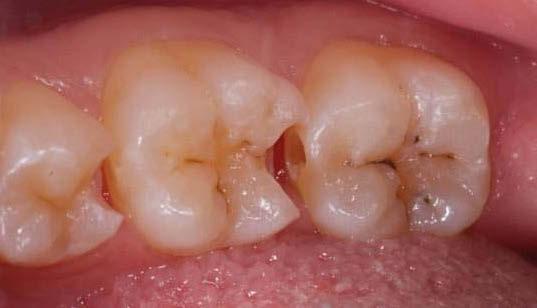

La exploración intraoral (figuras 4 a 8) revela una Clase II molar y canina completa, líneas 1/2 dentarias superior 0,5 mm e inferior 1 mm ambas desviadas hacia la derecha, los incisivos superiores excesivamente protruidos y vestibulizados (seguramente debido a la interposición del labio inferior), resalte de 13 mm y sobremordida 2/3 de corona. La discrepancia oseodentaria

inferior es de -3,5 mm y la curva de Spee de 4 mm.